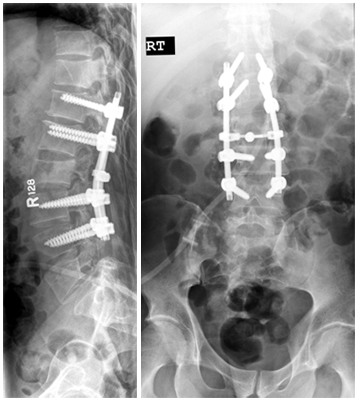

Upload Date: March 31, 2019 Full Size Image Dimensions: 358 × 400 Image Parent Post: Χειρουργική αντιμετώπιση καταγμάτων

3.Οπίσθια σπονδυλοδεσία για κάταγμα οσφυικού σπονδύλου